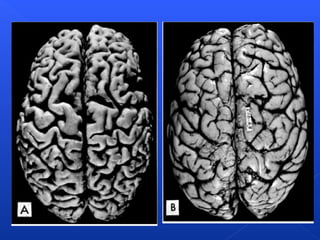

Atrophy of the brain

ATROFIA

Disminución del tamaño de células 

disminuye función de células-función del

órgano.

• Envejecimiento: En los tejidos que tienen células

permanentes como el cerebro y el corazón.